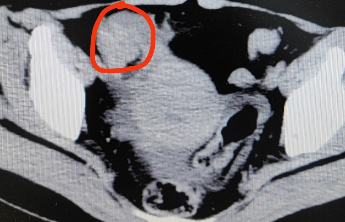

通讯员张男近日,泰安市中医医院心血管病二科成功开展首例AMC(主动脉瓣-二尖瓣交界区)起源室性心律失常射频消融术,标志着医院在复杂心律失常介入治疗领域取得新突破,也为实现“中医特色突出、现代技术卓越、综合实力雄厚、服务品质优良”的发展目标迈出坚实一步。患者为70多岁女性,因“胸闷、心慌10余年,加重1月”入院。心血管病二科副主任张立国详细询问病史并结合检查发现,其24小时动态心电图显示室性早搏达38025次,占比35.4%,伴发室性心动过速29阵共89次。患者曾于多家医院就诊,均因手术难度大、成功率不高,建议药物保守治疗。十年间症状反复,多次住院,深受疾病困扰。得知北京安贞医院专家定期来院手术